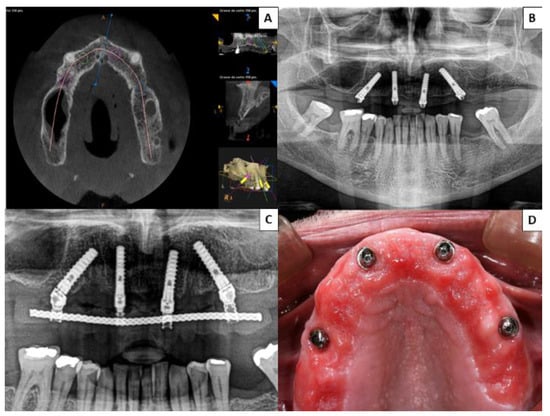

No prosthetic complications were recorded in Group 1 patients rehabilitated with zygomatic implants (either in provisional or definitive prostheses) (Figure 2), while three of the 40 patients (7.50%) treated by means of the all-on-four concept suffered prosthetic fractures, and another five (15.50%) presented excessive accumulations of food trapped apical to the definitive prostheses (Figure 3). None of the implants of this study failed, resulting in an implant cumulative survival rate of 100%. The cumulative survival rate for prostheses was 96.25%.

Figure 3. Group 2 patient rehabilitated with four conventional implants in the premaxilla following the all-on-four concept; two placed axially and the other two angled between 35° and 45°. (A) Presurgical planning with cone-beam computed tomography (CBCT) of implant distribution. (B,C) Postsurgical orthopantomographs taken 6 months after surgery to ensure correct fit of definitive prosthesis. (D) At a follow-up check-up, a patient complained of food debris trapped beneath the fixed prosthesis; when the prosthesis was unscrewed the patient was found to present mucositis.